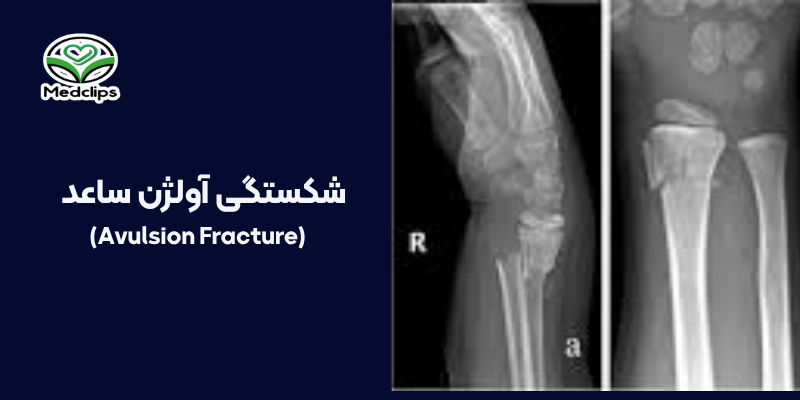

3. شکستگی آولژن

شکستگی آولژن زمانی رخ می دهد که:

- تاندون یا لیگامان

- در اثر حرکت ناگهانی و شدید

- به استخوان کشیده می شود

و تکه کوچکی از استخوان همراه آن جدا می شود.این نوع شکستگی بیشتر در فعالیت های ورزشی یا حرکات پرتابی و ناگهانی دیده می شود.اهمیت آن در این است که قطعه کنده شده باید در جای درست قرار بگیرد در غیر این صورت ممکن است باعث درد مزمن یا ناپایداری مفصل شود.درمان بسته یا جراحی بسته به اندازه قطعه جدا شده و میزان جابه جایی تعیین می شود.